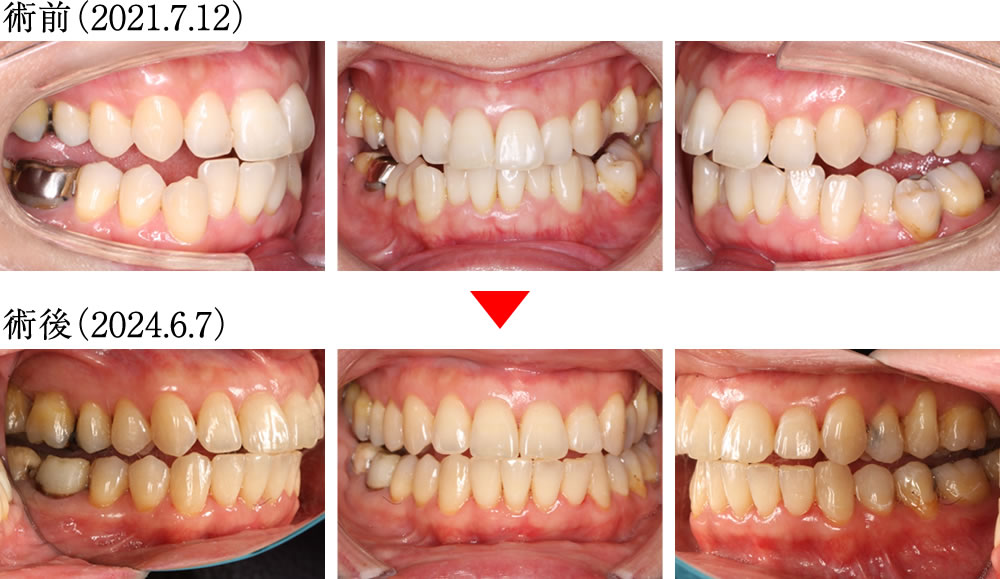

術前は前歯の噛み込みが深く、奥歯も正しく噛み合わない不安定な歯並びでしたが、術後は前歯から奥歯までバランスよく整い、理想的で美しい歯並びへと改善されました。

術前は歯列が狭く、歯並びも乱れていましたが、術後は歯列がダイナミックに拡大し、すべての歯が理想的に整列した美しいアーチとなりました。さらに親知らずも歯列に参加し、正しい位置に並んでいます。

左下の親知らずを有効に活用することで、咬合の再構成が可能となり、機能的な噛み合わせを実現しました。

術前は下顎を動かした際に犬歯が全く機能しておらず、不安定な噛み合わせでしたが、術後は前歯と犬歯が正常に機能するようになり、安定した理想的な咬合へと改善されました。